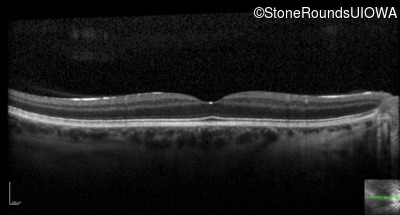

Optical Coherence Tomography - Left - 20/200

Exemplar / OCT Stack

OCT Stack